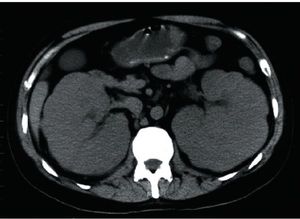

Acute Kidney Injury in Patients With Cancer

Acute kidney injury is a common complication in cancer patients, and clinicians should be familiar with the processes that cause it.